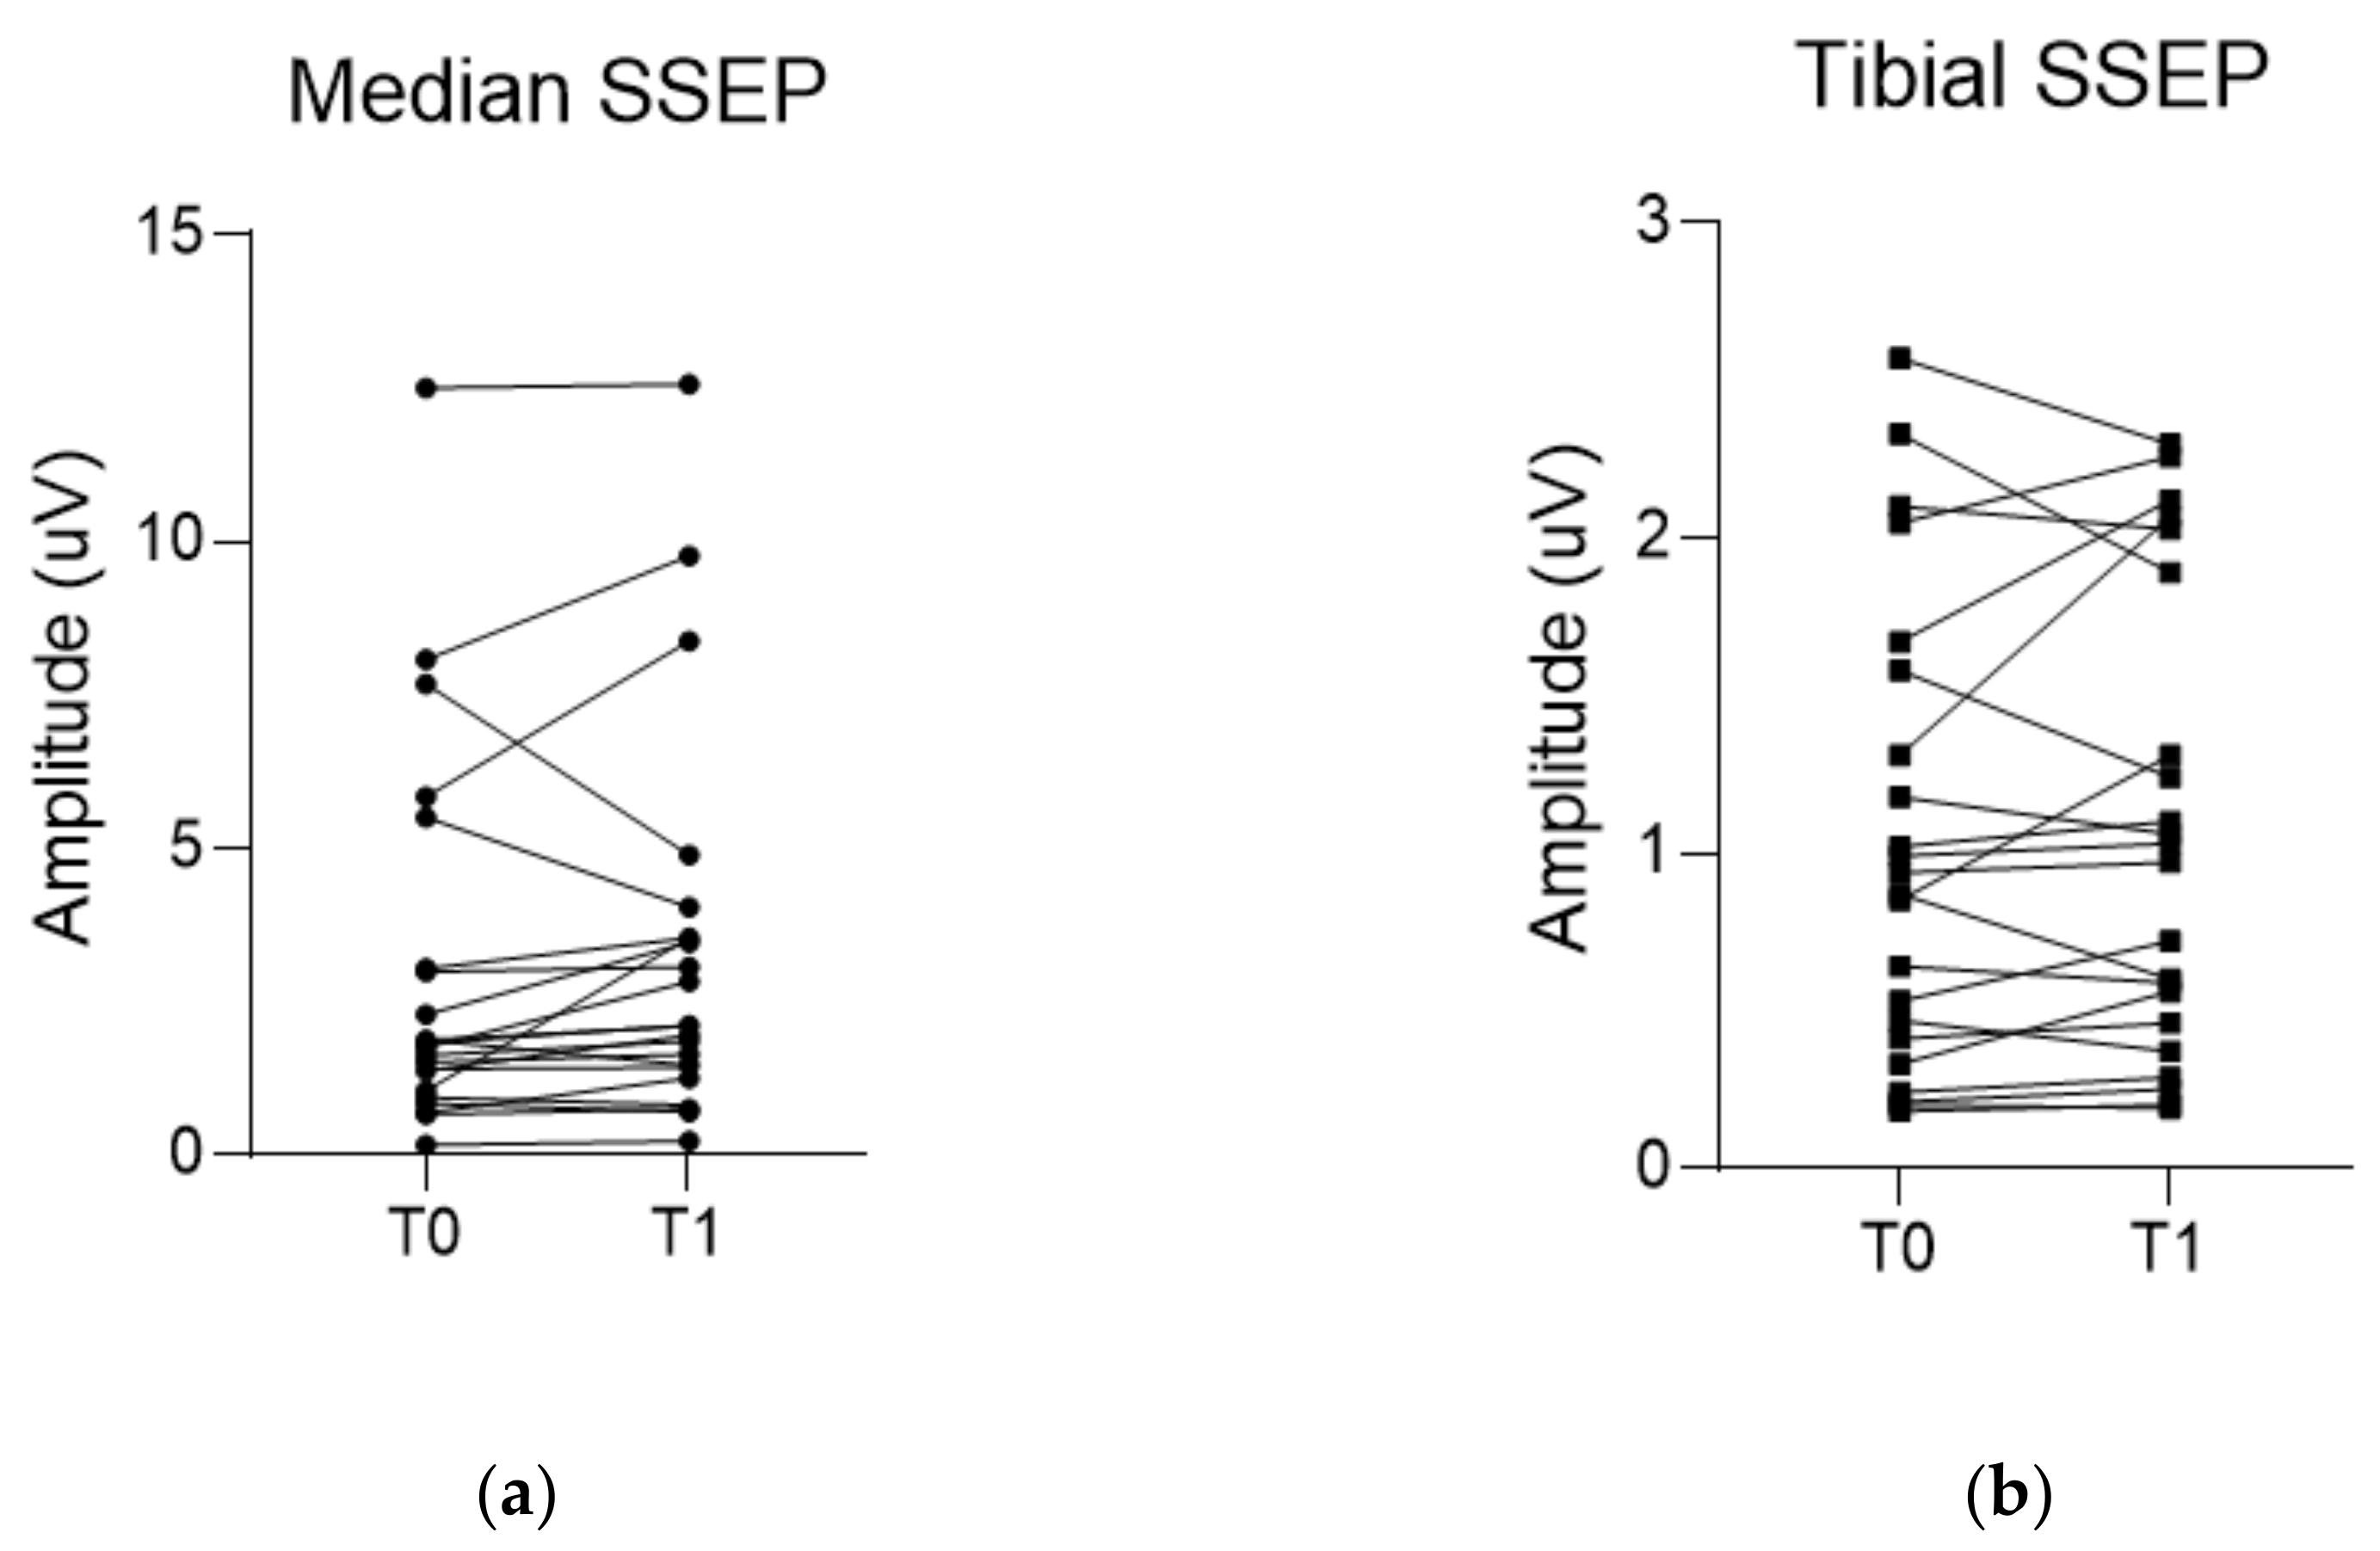

3.2. Comparison of EP Changes between the MB and MC Group

3.3. Changes in Examined Parameters and Their Correlations in the MB Group

| ΔMedian SSEP (%) | 13.8 (0.6, 41.3) | −4.3 (−19.8, 11.7) | 0.027 |

| ΔTibial SSEP (%) | 9.3 ± 26.8 | 1.5 ± 23.7 | 0.318 |

| ΔAPB-MEP (%) | 20.7 (5.6, 71.6) | 2.5 (−14.5, 12.9) | 0.006 |

| ΔAH-MEP (%) | 29.2 (8.6, 55.2) | 9.7 (−5.2, 28.2) | 0.015 |

| T0 a | T1 b | p-Value | |

|---|---|---|---|

| Median SSEP (µV) | 1.8 (1.0, 3.0) | 2.1 (1.4, 3.5) | 0.051 |

| Tibial SSEP (µV) | 0.9 (0.4, 1.6) | 1.0 (0.5, 1.9) | 0.604 |

| APB-MEP (µV) | 1318.9 ± 796.1 | 1793.2 ± 856.0 | 0.010 |

| AH-MEP (µV) | 1169.9 ± 576.2 | 1593.8 ± 721.6 | <0.001 |